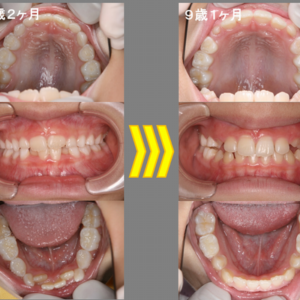

続きを読む下の前歯がガタガタでキレイにしてほしいと言ってきた7歳2ヶ月の女の子。下顎の6歳臼歯がかなり内側に倒れていて、前歯部の叢生量(スペース不足)が約5mmくらいになっています。上顎はキレイに歯が並んでいるように見えますが、乳 ...